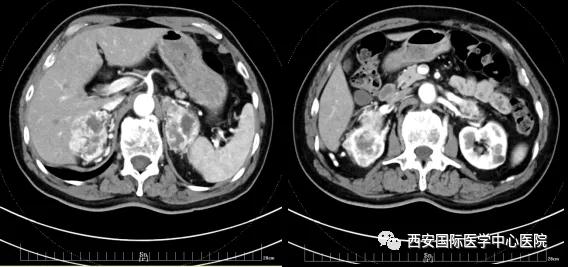

今年七十五歲的患者,來(lái)自陜西省商洛市,四月前因腰背部疼痛就診于當(dāng)?shù)蒯t(yī)院,行CT檢查發(fā)現(xiàn)“右腎、雙側(cè)腎上腺占位,前縱膈淋巴結(jié)腫大,雙肺多發(fā)結(jié)節(jié)、胸椎骨質(zhì)破壞,考慮轉(zhuǎn)移瘤”。為進(jìn)一步診斷治療,患者的兒子帶他來(lái)到西安某三甲醫(yī)院,查泌尿系CT提示“右腎占位性病變,多考慮腎癌,雙側(cè)腎上腺多發(fā)轉(zhuǎn)移灶,腹膜后多發(fā)腫大淋巴結(jié)”;行穿刺活檢提示“腎透明細(xì)胞癌”;并給予患者口服靶向藥物的治療方案。

自四月份至今,患者一直口服靶向藥物治療(阿昔替尼5mg 2次/日),期間無(wú)不良反應(yīng),目前腰背部疼痛癥狀也有所緩解,復(fù)查影像學(xué)資料提示瘤體較前縮小,腫瘤完整切除的可能性明顯提高;而且患者的兒子也是一名外科醫(yī)生,所以他更想為父親完成后續(xù)的手術(shù)治療。

患者一家慕名前來(lái)到西安國(guó)際醫(yī)學(xué)中心醫(yī)院找到楊增悅教授。楊增悅教授仔細(xì)看完患者的之前的影像學(xué)及病理資料后,診斷為:右腎透明細(xì)胞癌(T4N1M1);并安排他住院。而后,主管醫(yī)生及時(shí)為他完善了術(shù)前檢查及評(píng)估。7月15日,在麻醉手術(shù)中心柴偉主任、王彬榮副主任、李娟護(hù)士長(zhǎng)、李瑞剛護(hù)士長(zhǎng)及全體麻醉手術(shù)中心團(tuán)隊(duì)的有力保障下,成功完成了這臺(tái)“大”手術(shù)。